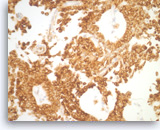

Pancreatic endocrine neoplasm #1,

Pancreas FNA, Cell Block.

The synaptophysin immunostain shows cytoplasmic positivity in the tumor cells, indicative of neuroendocrine differentiation.

40X

Pancreatic endocrine neoplasm #1,

Pancreas FNA, Cell Block.

The synaptophysin immunostain shows cytoplasmic positivity in the tumor cells, indicative of neuroendocrine differentiation.

40X